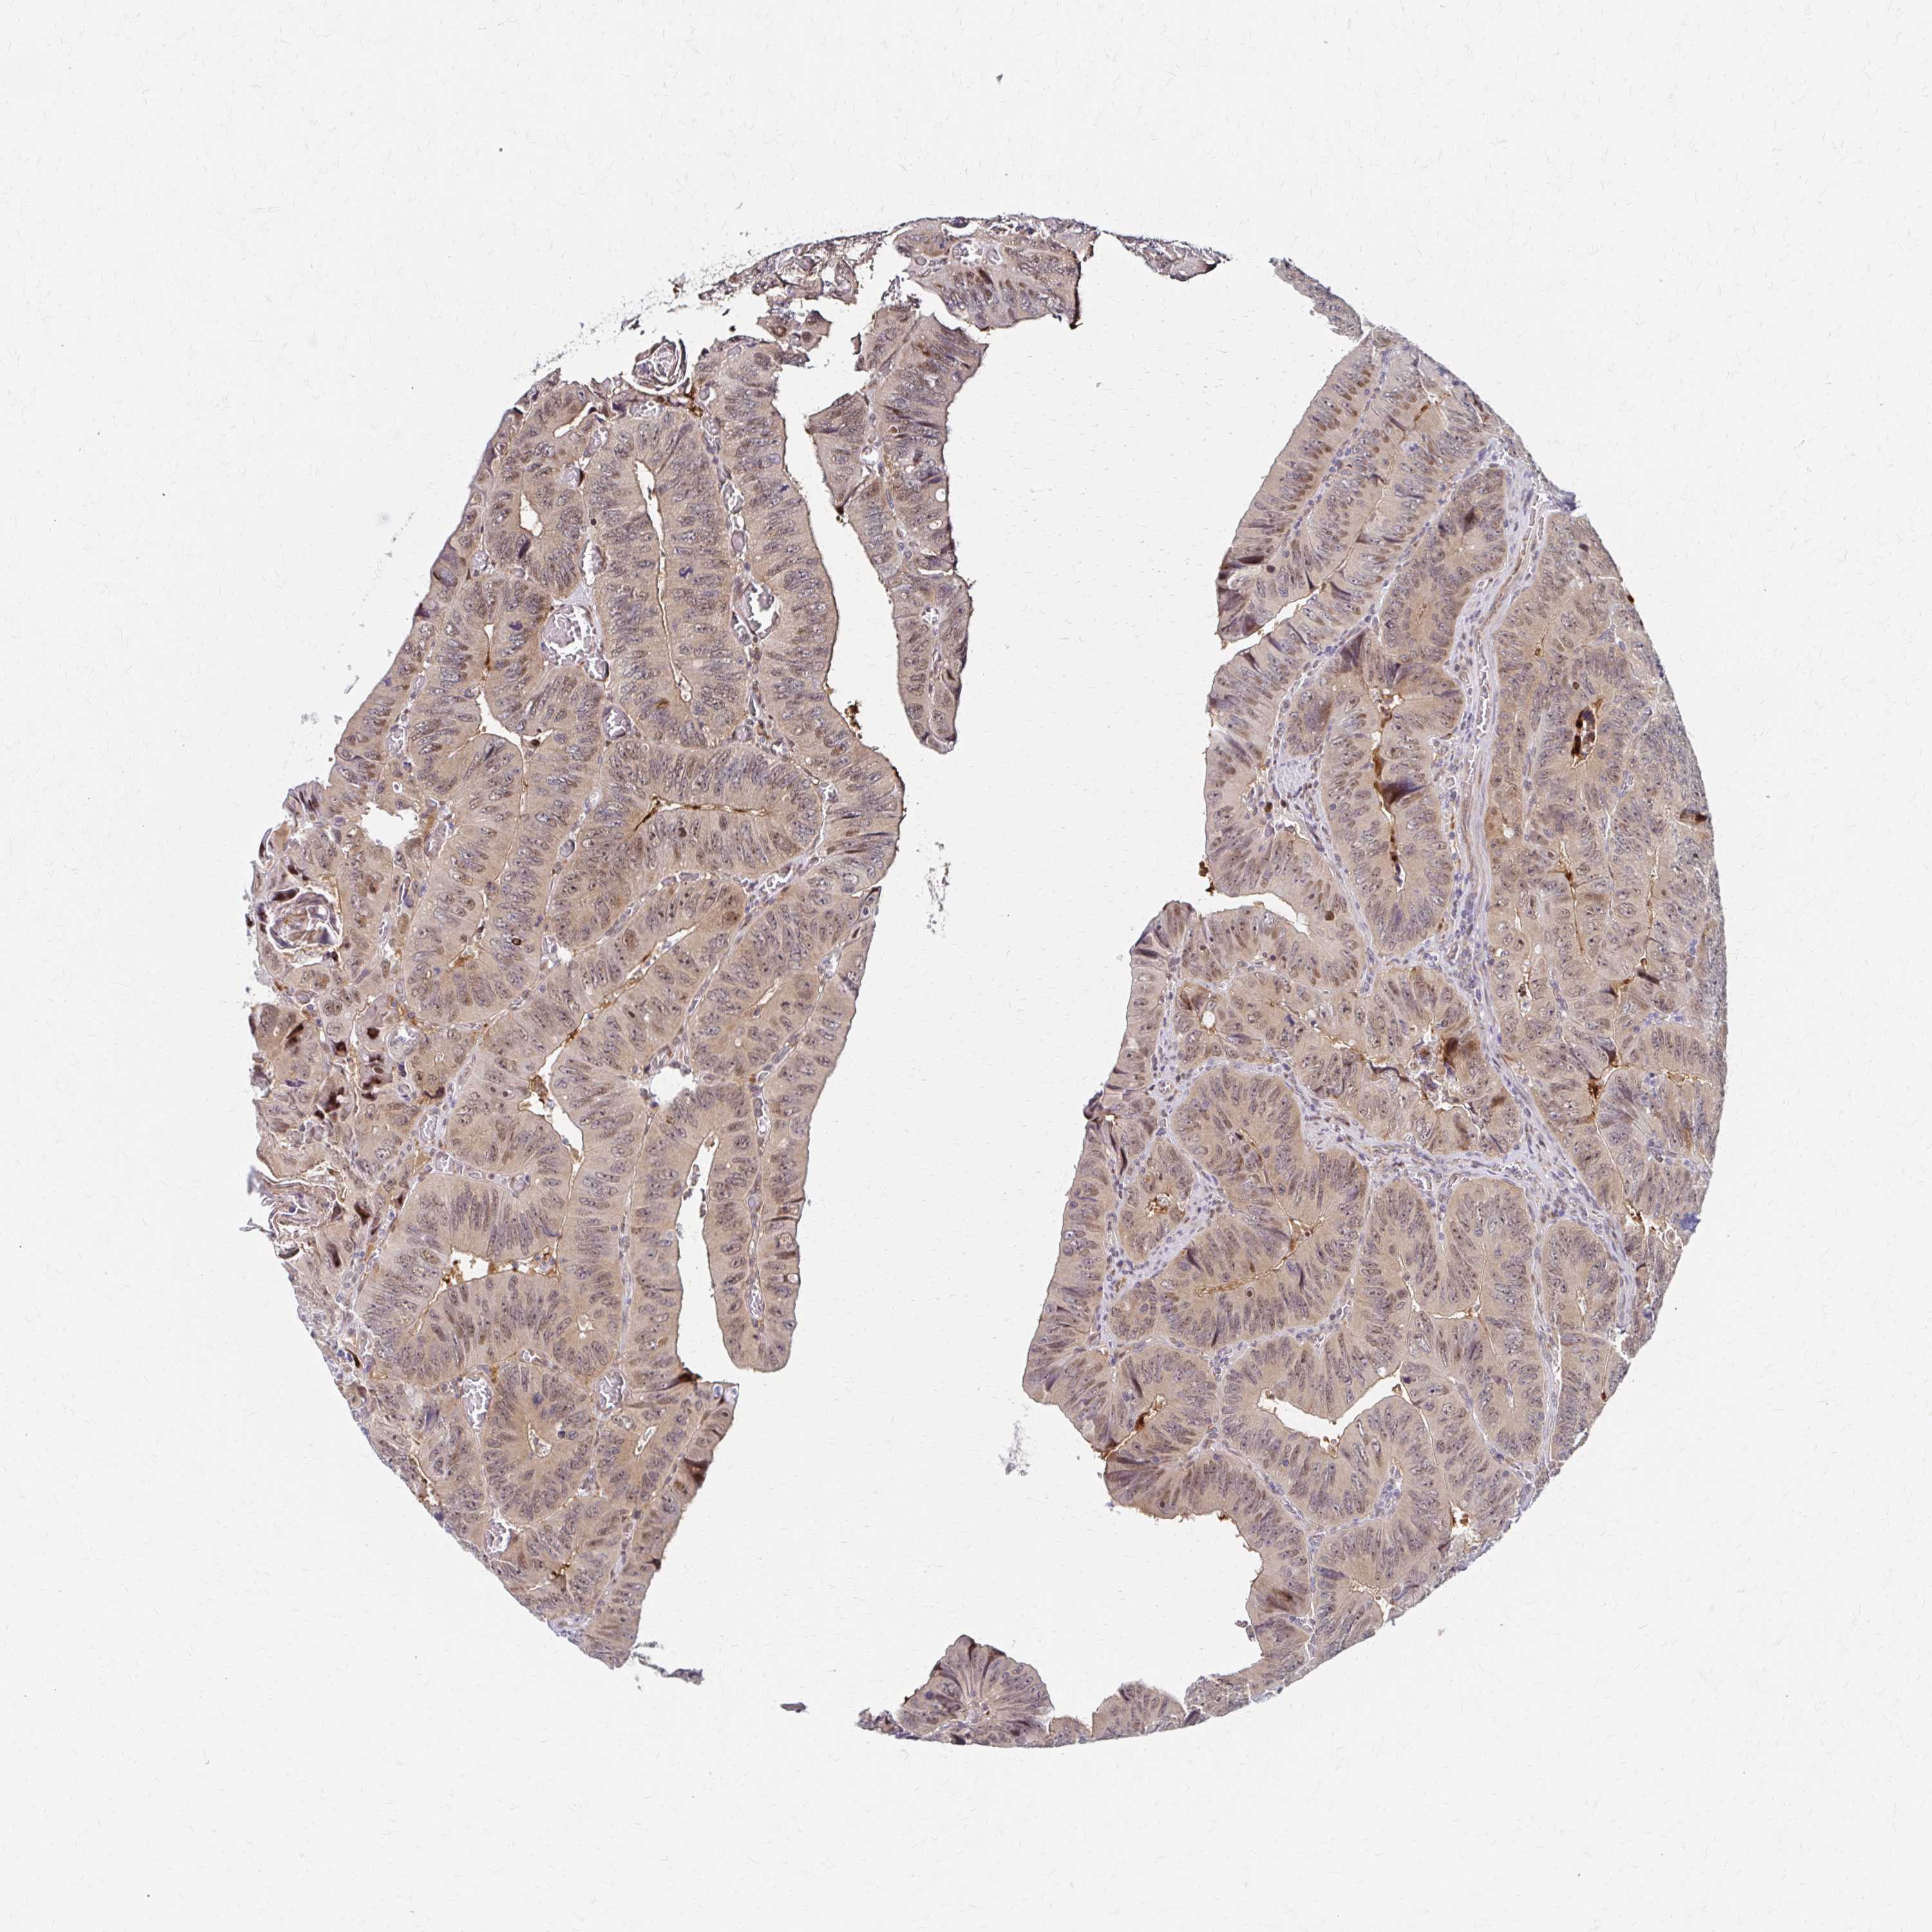

Colorectal cancer

Colon adenocarcinoma

TCGA RNA samplesi

RNA-seq data is reported as average FPKM (number Fragments Per Kilobase of exon per Million reads), generated by the The Cancer Genome Atlas (TCGA) .

Normal distribution across the dataset is visualized with box plots, shown as median and 25th and 75th percentiles. Points are displayed as outliers if they are above or below 1.5 times the interquartile range. FPKM values of the individual samples are presented next to the box plot.

Average pTPM 71.3

Number of samples 486